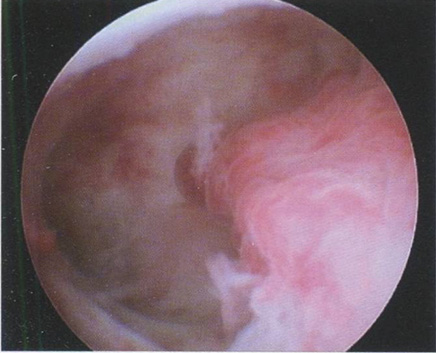

Рис. 3.4. Описание гистероскопической картины:

• полость матки треугольной формы, не деформирована;

• эндометрий бледно-розового цвета, в виде складок и гребней различной величины с жидкостными включениями. При изменениях давления за счет введенного расширяющего раствора отмечаются волнообразные движения эндометрия;

• устья маточных труб не визуализируются.

Заключение: гиперплазия эндометрия.

Гистологическое исследование: простая железисто-кистозная ГПЭ.

Такую картину можно увидеть в фазу секреции. Обычно в дне матки эти изменения выражены сильнее.